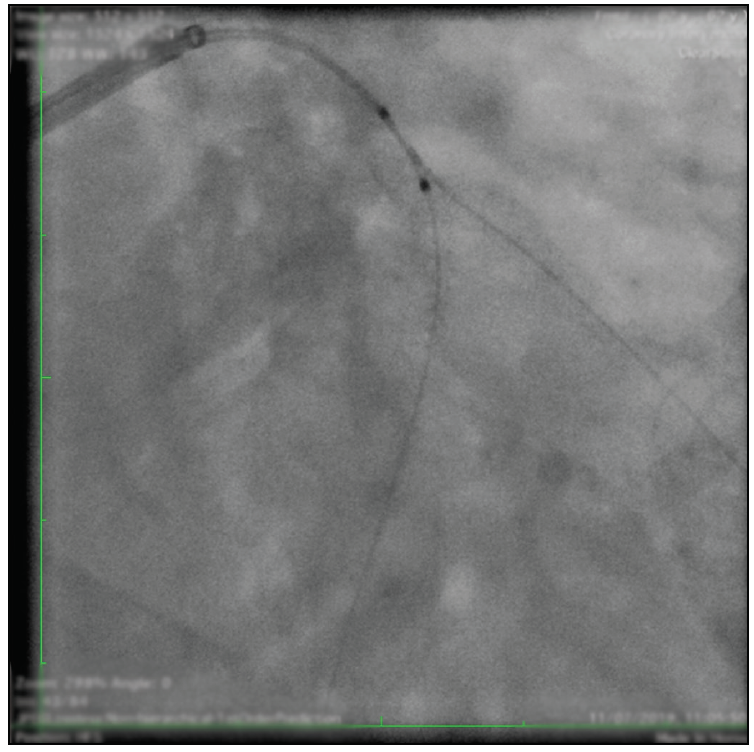

Two months later, the patient underwent percutaneous coronary intervention (PCI) in a staged procedure targeting the LCX. After receiving a 600-mg loading dose of clopidogrel orally and intravenous heparin and nitrates, access was achieved through the right femoral artery with angiographic guidance using a 7-F XB 3.5 Vista Brite Tip catheter (Cordis, a Cardinal Health company) to visualize the target lesion. A Runthrough NS Floppy guidewire (Terumo Interventional Systems) was used to progress and position a FineCross MG microcatheter (Terumo Interventional Systems) at the proximal tip of the LCX lesion (Figure 2). Two Fielder XT-R guidewires (Asahi Intecc USA, Inc.) were passed to the LCX and OM1, respectively. However, after crossing to the distal LCX, the microcatheter did not advance to the OM1 branch.